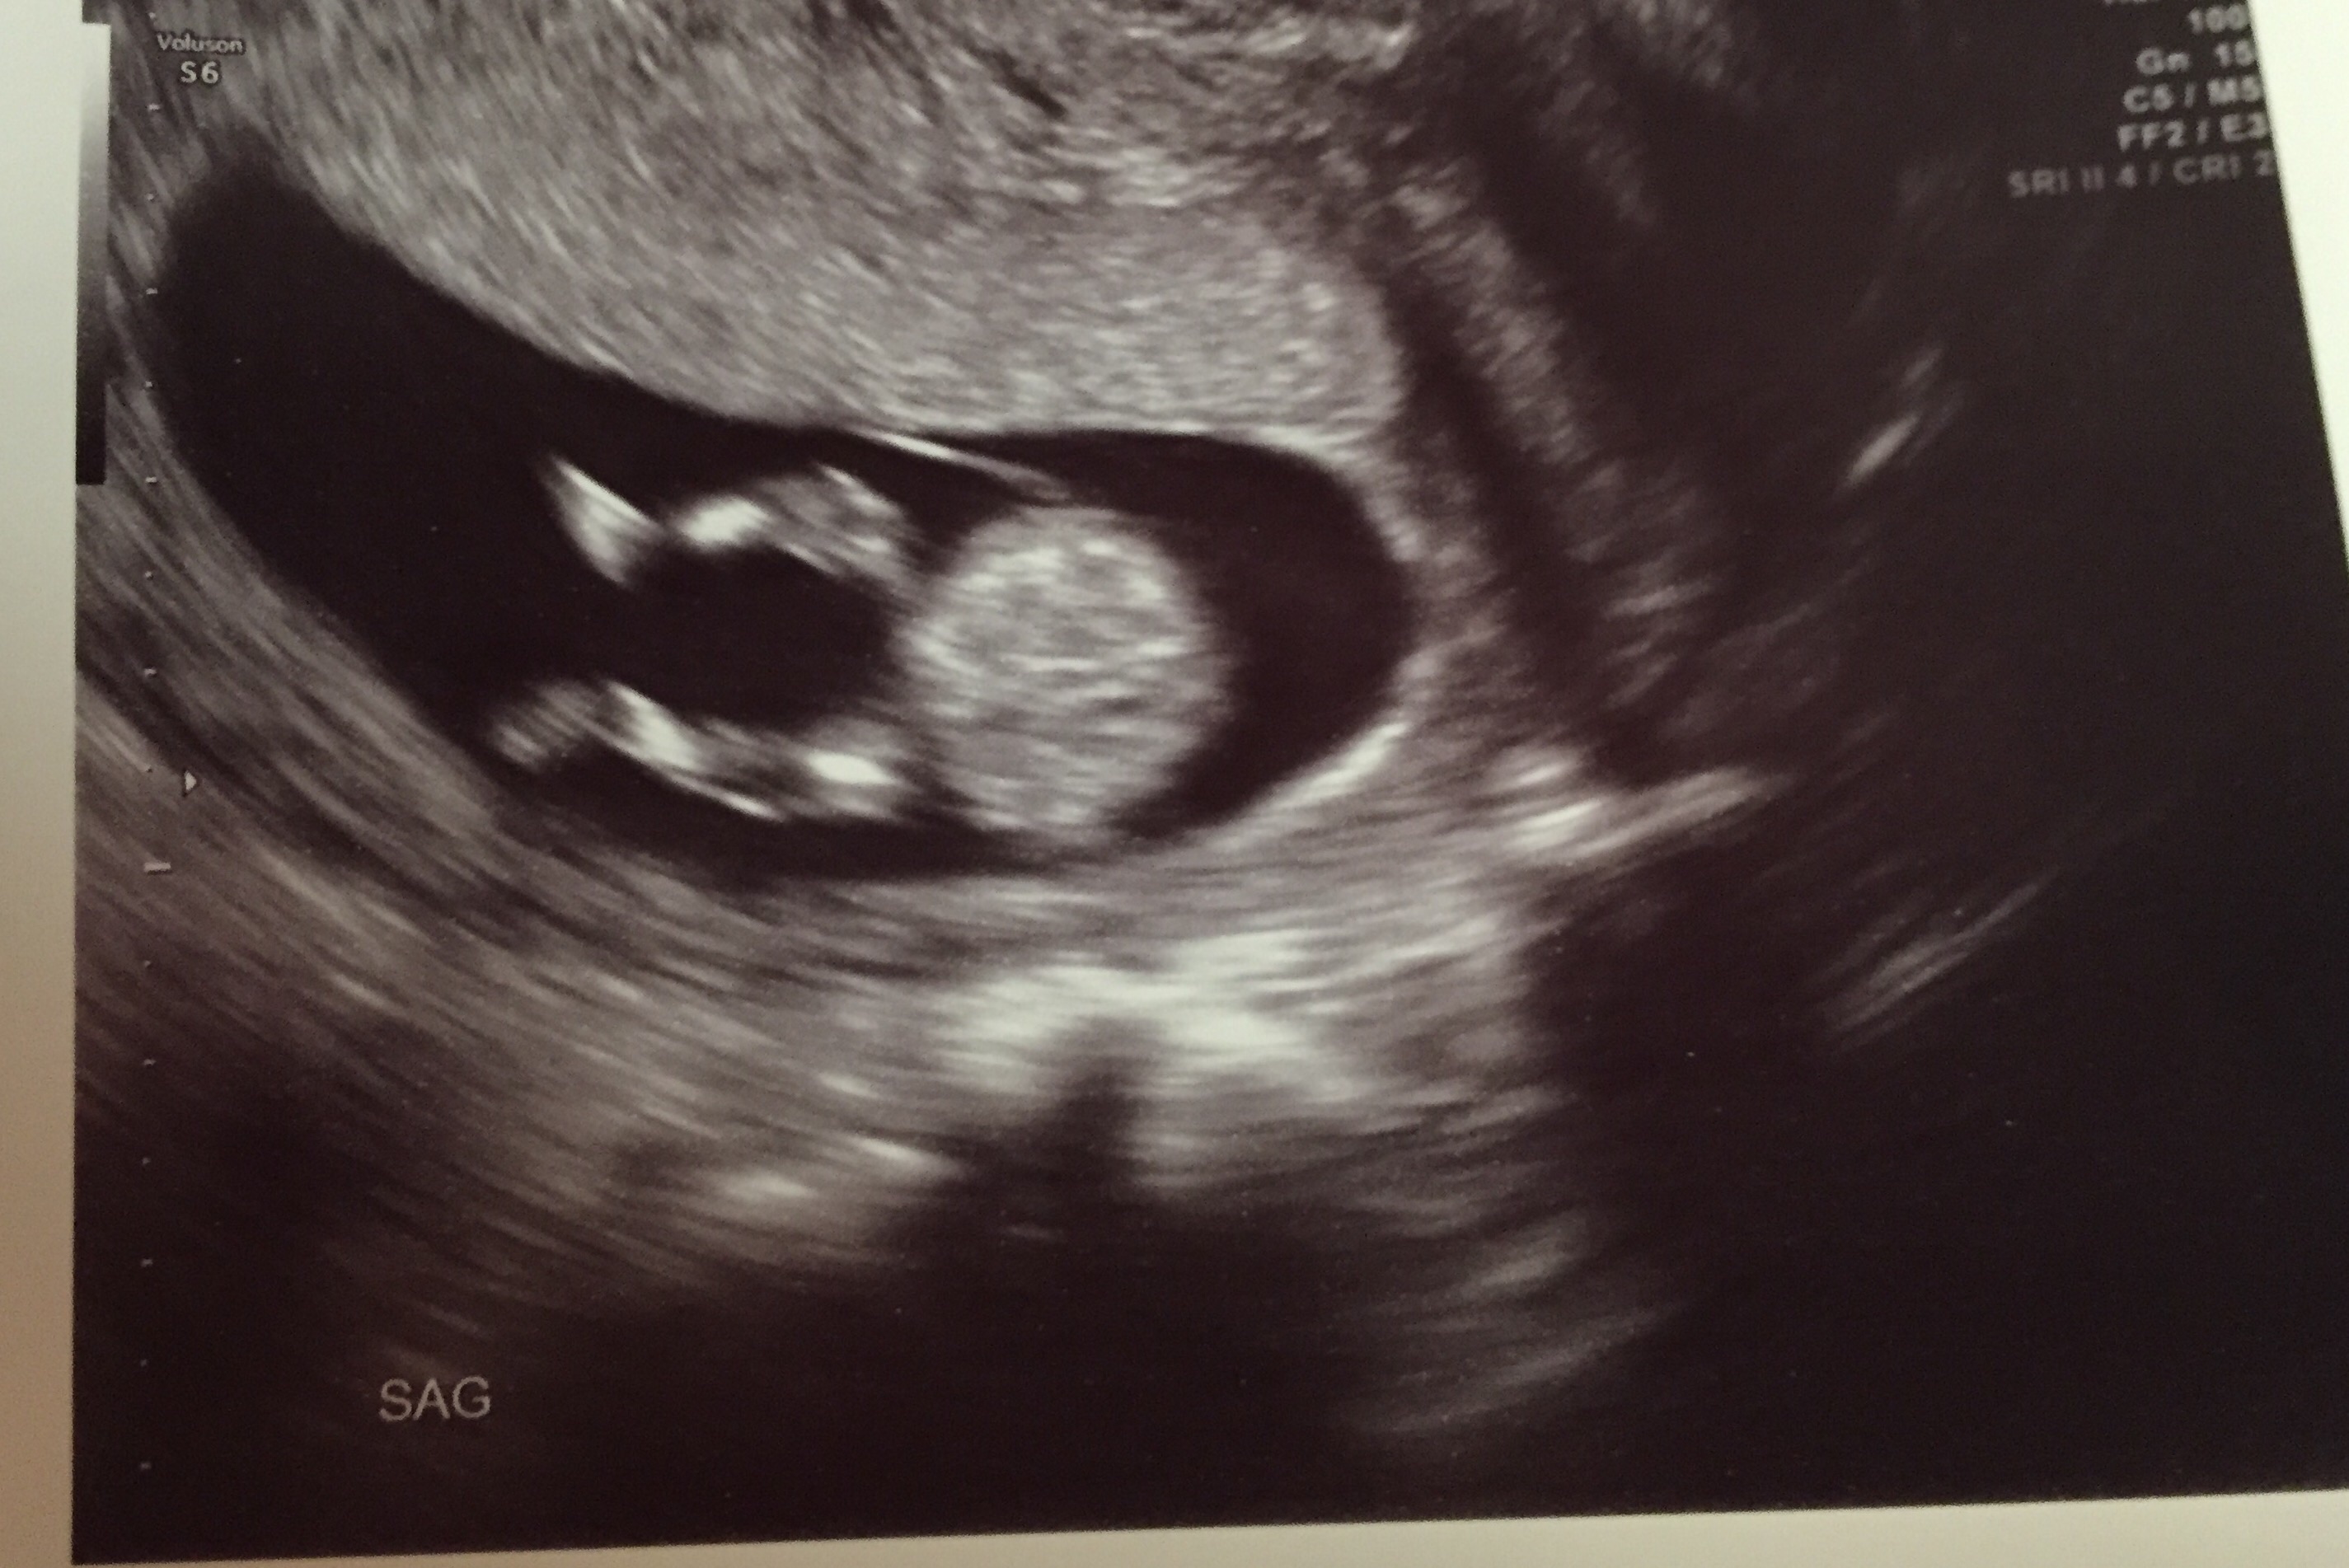

All looked good in the scan. Wiggles was moving all around and being really cute. The tech took a guess at the gender and we will get the results of all of the bloodwork next week. I'm just feeling happy. Look at those cute legs! Hope everybody gets good scans and has a great week.

I felt like I had a sore uterus the day after too. The office didn't realize that I was doing the nt scan so they didn't tell me to have a full bladder. We still saw wiggles just fine but I think she had to get in deep to do so.